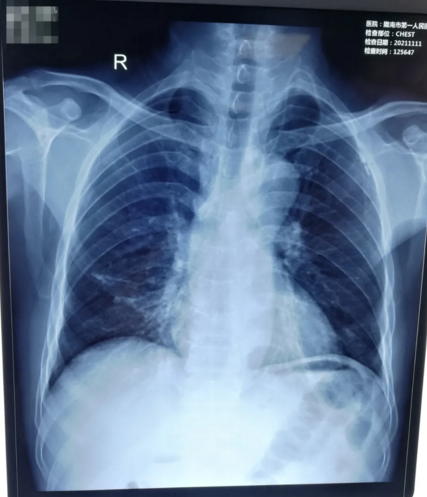

11月11日,我院胃肠外科/肿瘤外科自主成功开展了一例胸壁输液港植入术,此项技术被称为“肿瘤患者的避风港,看不见的生命线”,填补了我市完全植入术静脉给药装置技术的空白,为长期需要静脉治疗的患者带来了福音。

患者刘某某,男,56岁。因“左下腹疼痛7天,加重伴恶心呕吐半小时。”急诊入我院。入院行相关术前检查后诊断为:急性肠梗阻,直肠恶性肿瘤。积极完善各项术前化验检查,急诊在全麻下行剖腹探查、乙状结肠造瘘术。考虑到患者术后需进一步手术及术前、术后需多次化疗,与患者家属积极沟通后决定行胸壁输液港置入术。

手术由胃肠外科/肿瘤外科副主任医师冯叶主刀、护士长杨珂,重症医学科主治医师周海洋、主管护师王武燕紧密配合、通力协作,在患者颈部超声引导下快速、准确的穿刺颈内静脉,将预设长度导管通过穿刺点置入上腔静脉,再于胸壁做囊袋,固定港座,切口行皮内缝合。手术顺利,用时仅有35分钟,患者无任何不适。